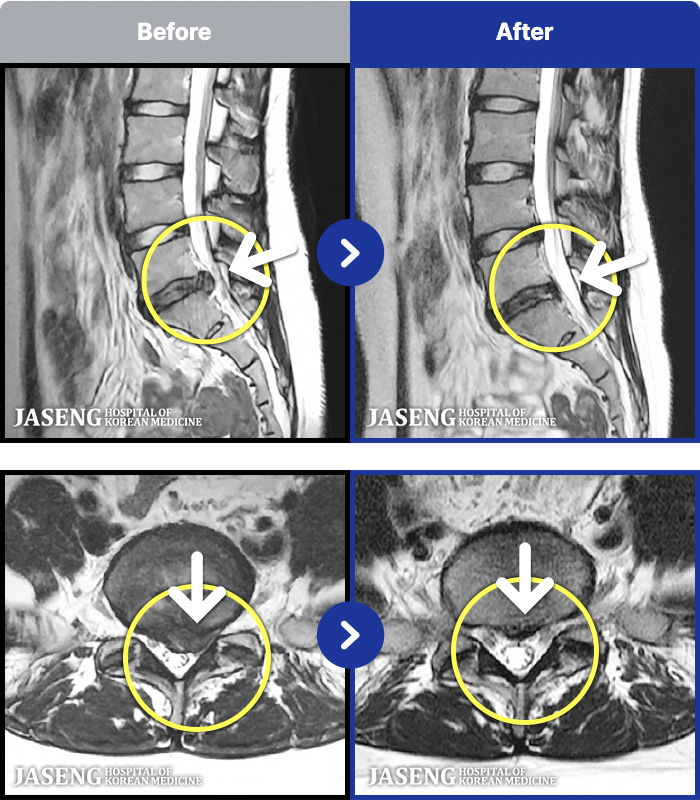

MRI ġ

1,237 MRI ũ ʸ Ȯϼ.